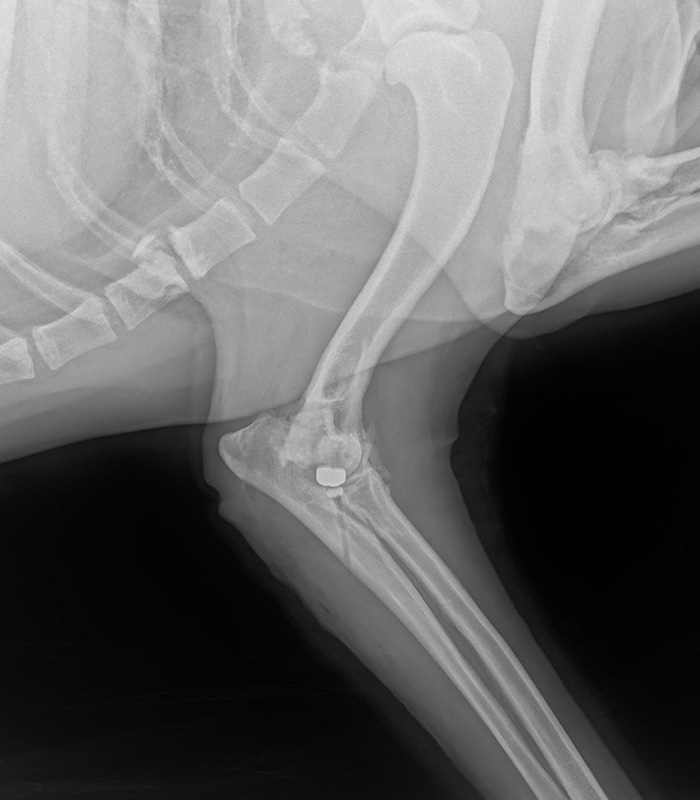

Postępujący proces zwyrodnienia stawu łokciowego w przebiegu dysplazji rozpoczyna się od strony przyśrodkowej stawu.

Osteoartritis przy zaawansowanej chorobie wyrostka wieńcowego w przebiegu dysplazji stawu łokciowego generuje zanik chrząstki przedziału przyśrodkowego stawu. Wzajemny konflikt powierzchni stawowych prowadzi do ich niszczenia, wycierania się, i w efekcie do tzw. end stage form of elbow, powstawaniem odczynów wytwórczych, ograniczeniem ruchomości stawu, silnym bólem i dysfunkcją motoryczną. U zdecydowanej większości pacjentów zmiany zachodzące w tzw. przedziale przyśrodkowym długo nie mają wpływu na zdecydowanie większą część boczna stawu która zachowuje swój status anatomiczny.

Zabieg artroplastyki CUE rozwinięty przez dr. Schulz i dr. Cook przy współpracy z firmą Arthrex jest dedykowany dla pacjentów z MCD (medial compartment disease). Technika została opracowana dla tych pacjentów u których standardowe postępowanie z zastosowaniem artroskopii czy innych form leczenia operacyjnego (osteotomie dystalna, podwójna skośna, PAUL, SHO) z racji zaawansowania procesu nie są wskazane.

Operacja CUE polega na zainstalowaniu dwóch implantów –w kość ramienną oraz łokciową w miejscu istniejącego konfliktu w stawie. Większy implant dedykowany dla kłykcia kości ramiennej jest zbudowany ze stopu kobaltu chromu i tytanu, mniejszy powstały z mieszanki polietylenu i tytanu umieszczamy w kości łokciowej. Prawidłowo wykonany zabieg prowadzi do odbarczenia niszczonej powierzchni stawowej, a wzajemny stosunek pracy powierzchni powstałej protezy generuje powrót funkcji i prowadzi do zwiększa zakres ruchomości stawu.